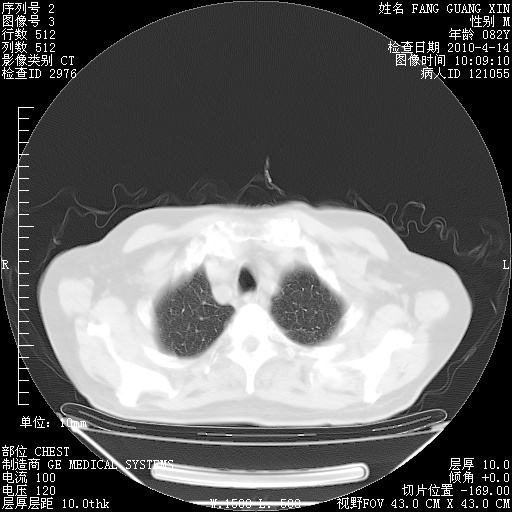

4月14日肺部CT